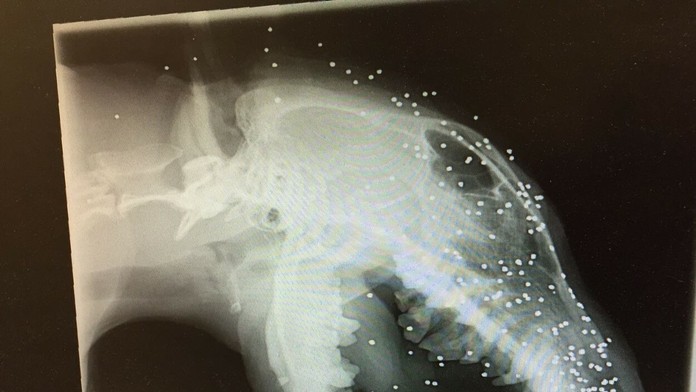

Anglického bulteriéra Erica strelili do tváre z bezprostrednej vzdialenosti, do hlavy sa mu zavŕtalo okolo 50 maličkých brokov.

Niektoré sa dokonca dostali až do jeho lebky. Hrozná udalosť sa stala v Turecku ešte v marci 2015, potom si ho adoptovala Britka Liz Haslam, ktorej nebol jeho osud ľahostajný a psíka sa snažila za každú cenu aspoň v rámci možností vyliečiť. Pani Haslam prevádzkuje útulok pre týraných psov.

Otrasné na celej veci je, že ani ona o guľkách v tele psa nevedela. Ericovi však opuchlo ucho a musel ísť na röntgen a ten odhalil šokujúcu pravdu o jeho stave. Lekári aj pani Liz zostali v úplne šoku. Na snímke sa objavili desiatky maličkých brokov.

Vedeli, že Eric je takmer slepý, no až teraz pochopili, že to spôsobil výbuch. Nakoniec sa ukázalo, že opuch ucha spôsobil zub iného psa, vrastený do Ericových úst. Fotografie ukazujú jeho úbohý stav.

Keď objavili guľky, veterinári jej povedali, že s tým sa nedá už nič robiť a pes s nimi aj zomrie. Podarilo sa im odstrániť aspoň vrastený zub, čo pani Liz stálo 800 eur.